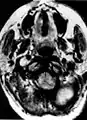

Glomus jugulare tumor

Ectopic functional paraganglioma (glomus jugulare) in a patient with VHL. T2 weighted MRI at the same location demonstrates a high signal mass consistent with a paraganglioma. Extra adrenal paragangliomas can be found in VHL (arrow).